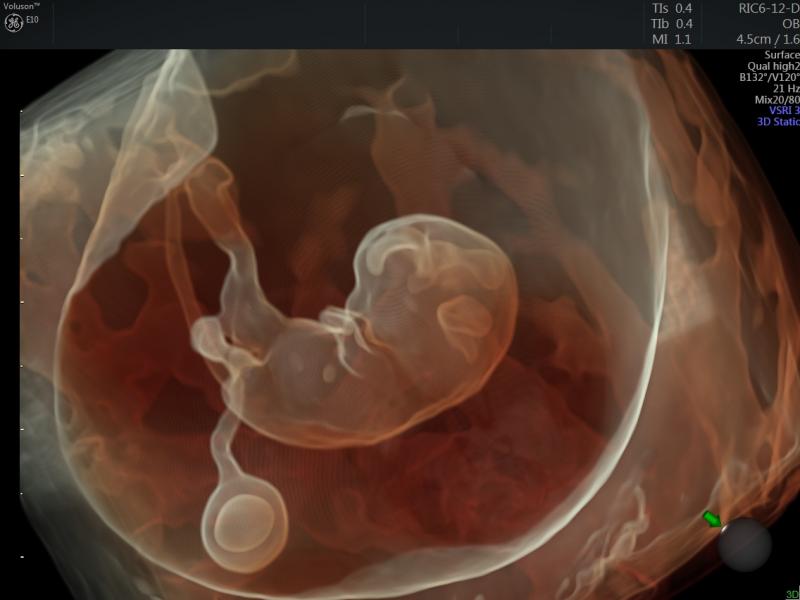

Below is a collection of prenatal ultrasound pictures from the Imaging Technology News (ITN) archive. Use the arrows to ...

September 19, 2017 — Philips announced new OB/GYN innovations at the 27th World Congress on Ultrasound in Obstetrics and ...

May 10, 2017 — Philips announced the debut of its TrueVue, GlassVue and aRevealA.I. capabilities on the company’s Epiq 7 ...